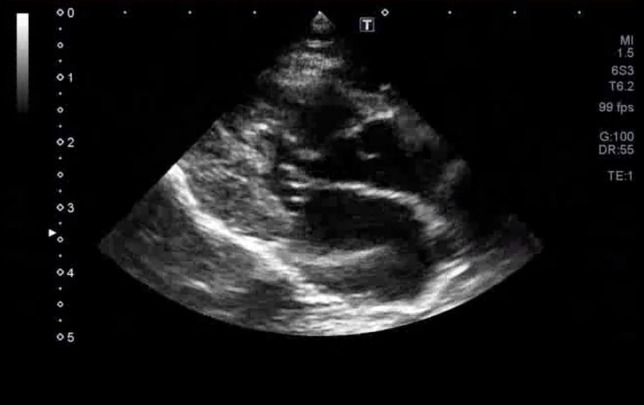

図3C 心原性肺水腫の猫における肺超音波画像

雑種猫、8歳5カ月齢、去勢雄、体重4.68kg。心疾患の管理中であったが、3日ほど投薬できておらず、かかりつけ医より紹介来院した。肺水腫によりB-lineの増加(white lung)が認められた。

特集 悩ましい猫の肺炎 vs. 肺水腫 vs. 肺腫瘍(塗木貴臣先生)図3Ⅽ